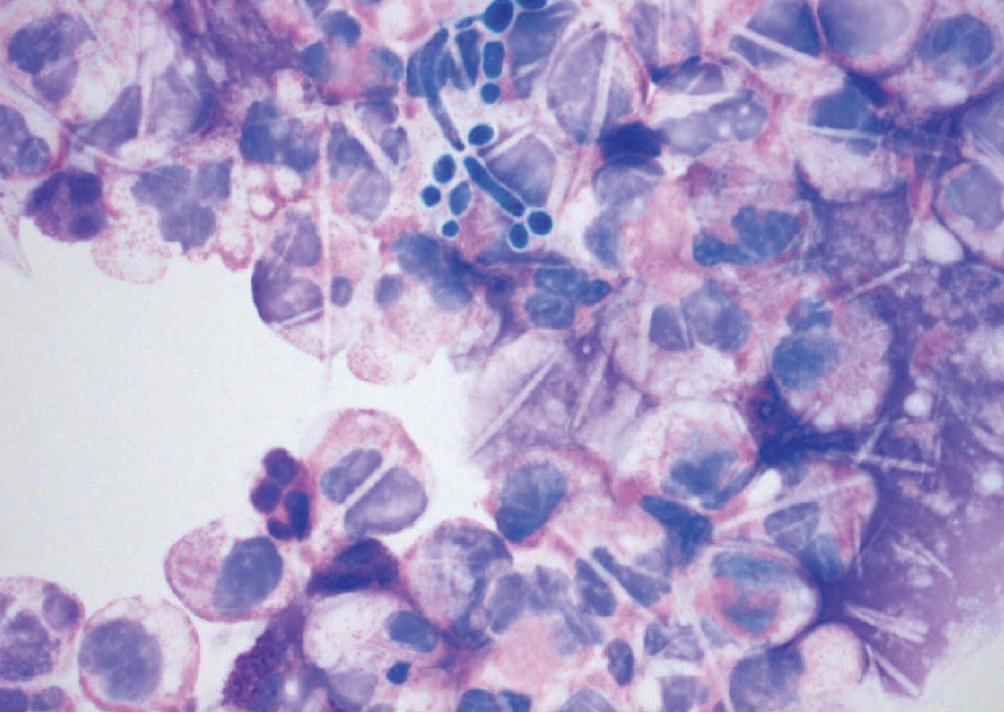

Ahmed Raziuddin, MD; Mohammed Hassan-Ali, MD, MSc; Mohemmad Abbas, MD

A 25-year-old man presented with a 4-day history of sudden pain in the left lower quadrant, leading to the primary care provider's initial diagnosis of diverticulitis.